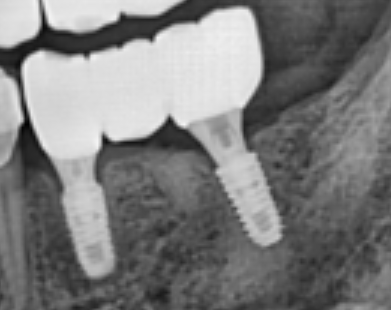

위 사진은 어금니 부위에 2개만 심고, 치아 3개의 역할을 복구한 모습입니다. ^^